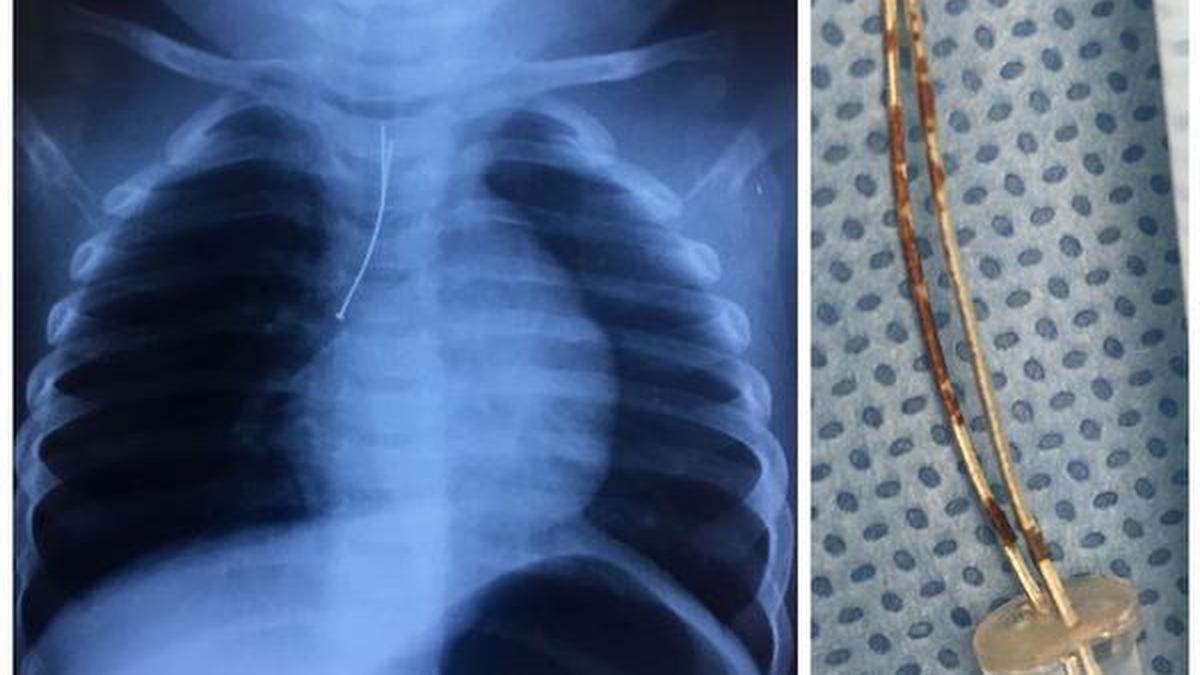

In young children the patient lies on the table and the hands are held above the head. Baby chest x ray tubechest trochar cannula appropriate for baby 3 way tap 10 ml syringe skin disinfectant. It can detect signs of pneumonia a collapsed lung heart problems such as an enlarged heart.

Are you in America. An X-ray can determine whether a childs heart or lungs look normal. It turns out this photo originally posted on Reddit of a baby squished into a tube like a lil baby deposit is actually of him getting a tiny X-ray.

10 Month Old Baby Swallows Led Bulb The Hindu